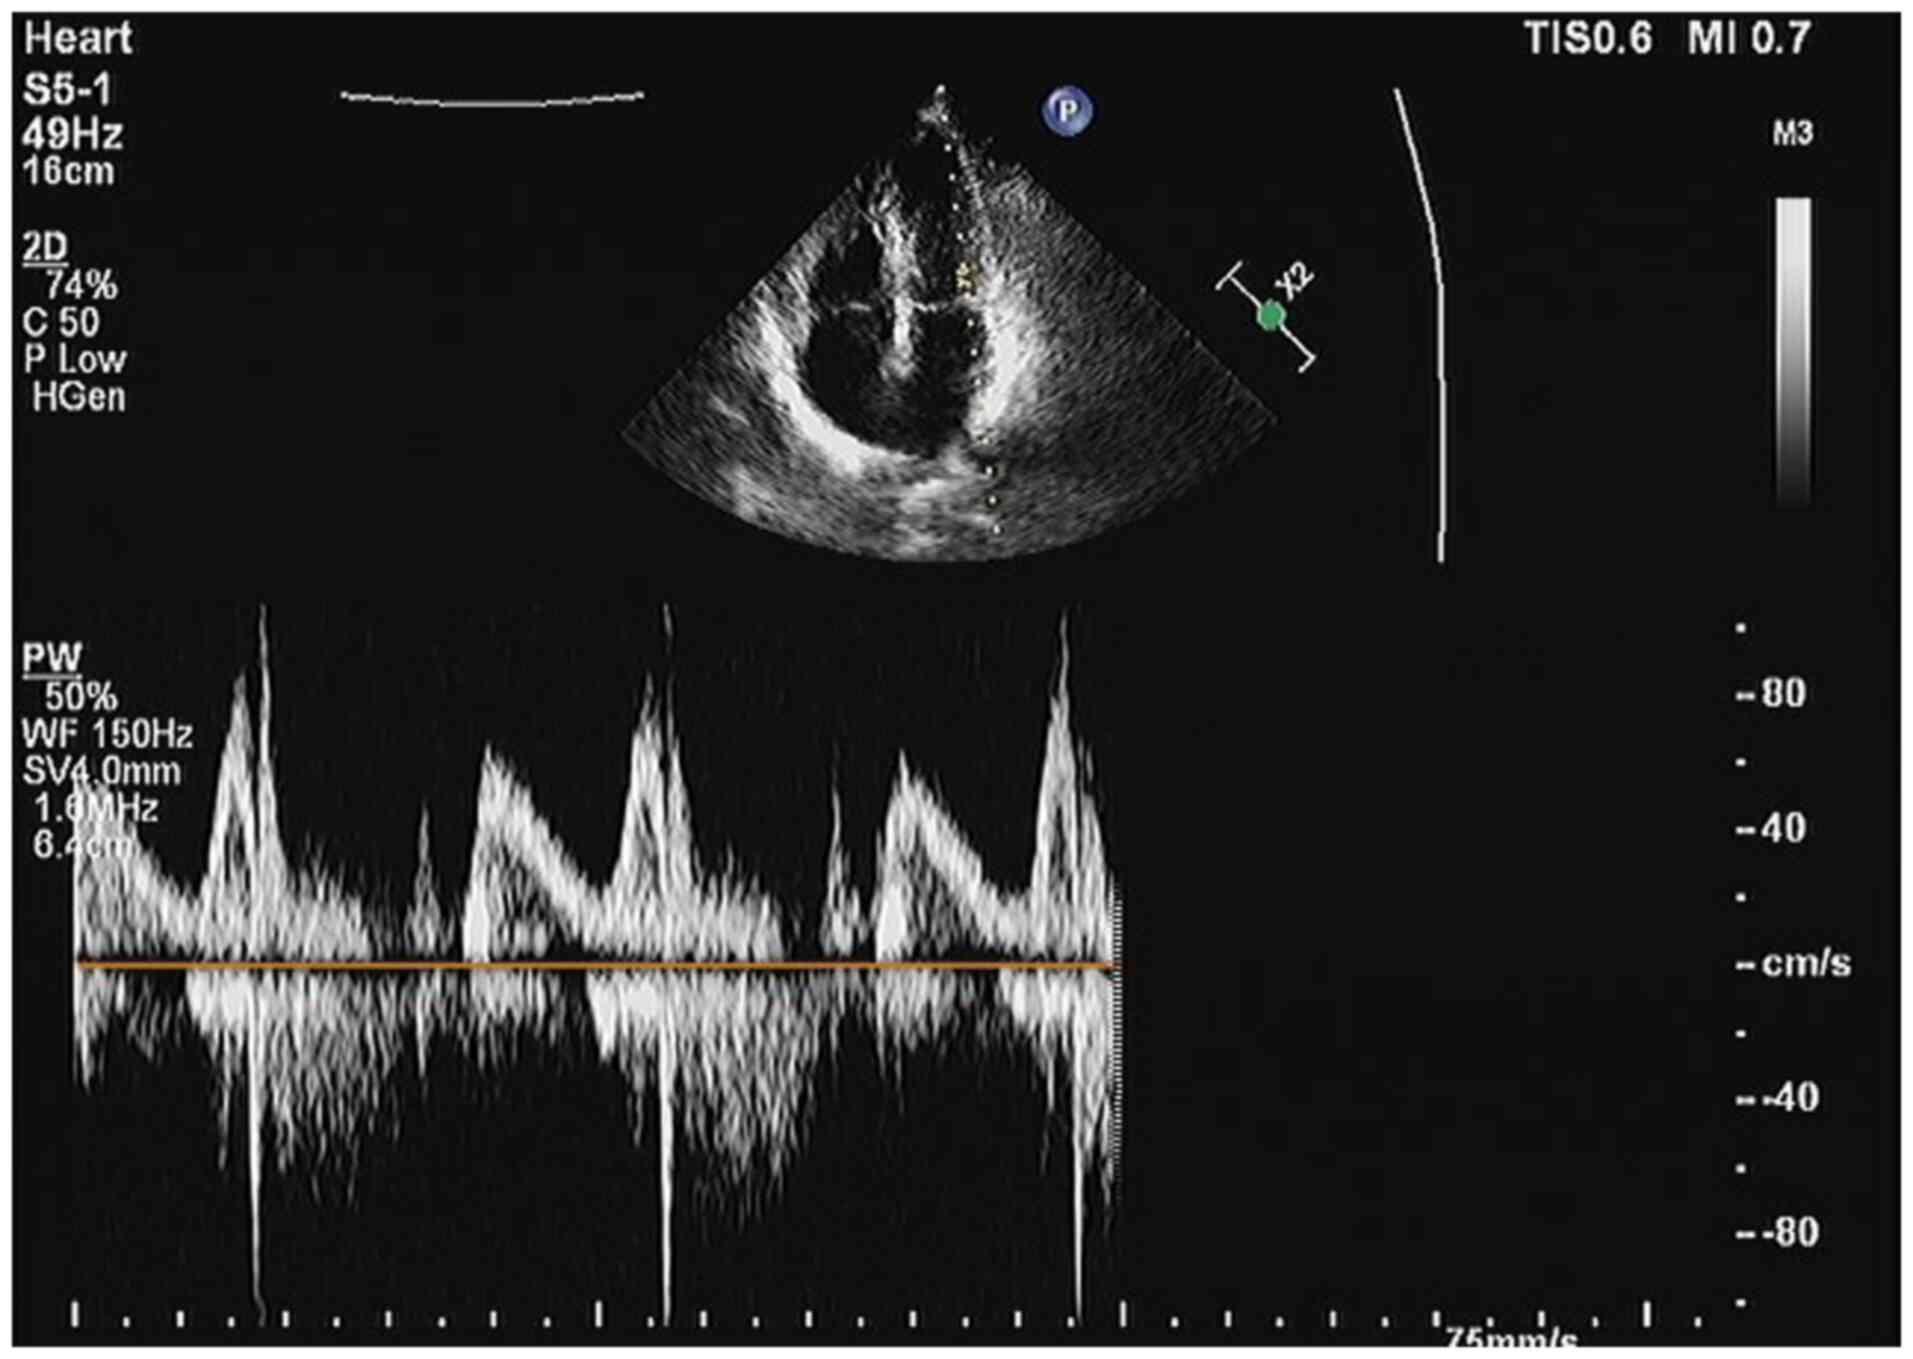

Coronary angiography combined with stenting was proposed on Day 4

to determine the cause of the patient's condition. A cardiac

ultrasound determined that the patient did not have a medically

significant myocardial infarction (Fig. 6). Cardiac angiography showed that